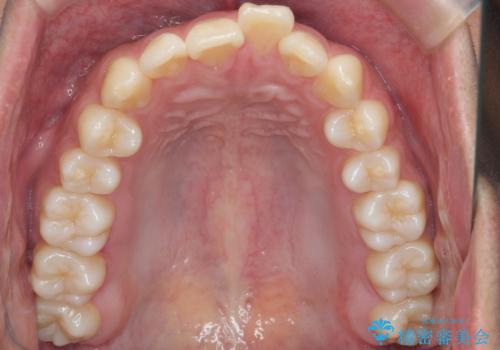

出っ歯の治療 インビザラインで抜歯矯正 親知らずを使用した矯正

- 出っ歯を主訴に来院。

上の小臼歯を2本抜歯しています。

そのかわり、上の親知らずを生かしており、歯の本数は減っていません。

奥歯の歯ならびのずれが大きく、親知らずを抜いてすべて後ろに下げるか、手前の歯を抜いて前歯を下げるかの2択でした。

時間はかかりましたがしっかり前歯を下げて治療しています。